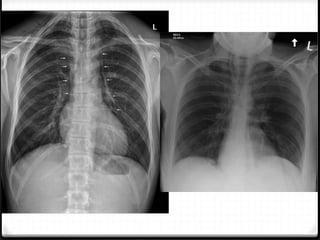

Fraktur costae

0 Most common skeletal injury (± 50%)

0 Simple ribs fracture rare life threatening

0 Multiple  more severe injury  ↑ morbidity & mortality

0 Location of fracture

0 X-ray and CT

 x-ray : limited sensitivity, helpful >>  Oblique >> AP/PA

 CT scan : most sensitivity